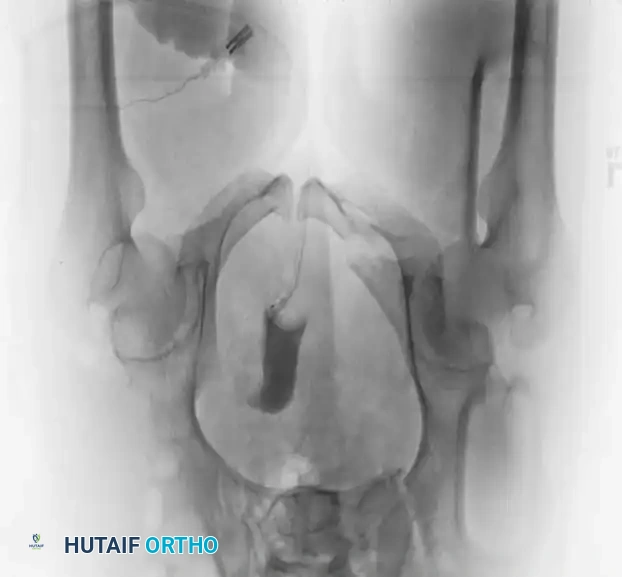

The following gallery demonstrates the progression of complex pelvic ring reconstructions, highlighting advanced imaging, intraoperative fluoroscopy, and definitive fixation constructs.

Advanced Imaging and Preoperative Planning

Image